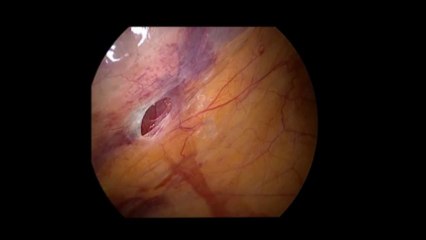

Laparoskopi ile Endometiroma (Çikolata kisti) operasyonu 1 - Prof. Dr. Aydan Biri

Laparoskopi ile Endometiroma (Çikolata kisti) operasyonu 1 - Prof. Dr.